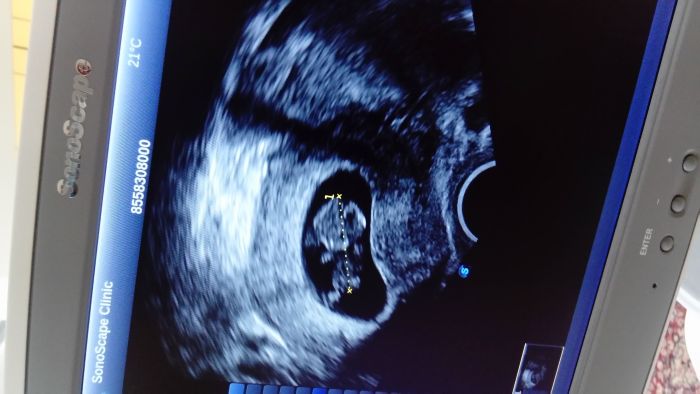

My mame po prvnim screeningu,byl to krasny zazitek.Krev na placentarni hormony je vporadku a UTZ tez.Miminko ma 7,5 cm a dokonce nam bylo sdeleno ze na 65% holcicka.To jsem teda cumela.Pri prvorozenej (pred 16i lety jsme se to dozvedeli tak nejak dva mesice pred porodem) a malej pred trema roky se taky statecne schovaval az do 20.tydne

[993147] Jé, to je krásný Lindi, moc gratuluju pravděpodobně k princezně :) jak dlouho ti dělali ten UTZ? Já jdu za týden a jsem hrozně nervózní, od začátku taky tuším, že to bude holčička, s jinou variantou ani nepočítám :D tak jsem zvědavá, jestli už nám taky řeknou :) Dostali jste fotečky?

UTZ byl opravdu hodne podrobnej,a jelikoz miminko ne vzdy spolupracovalo hned jak pan doktor potreboval,snimali jsme neco pres pul hodiny.